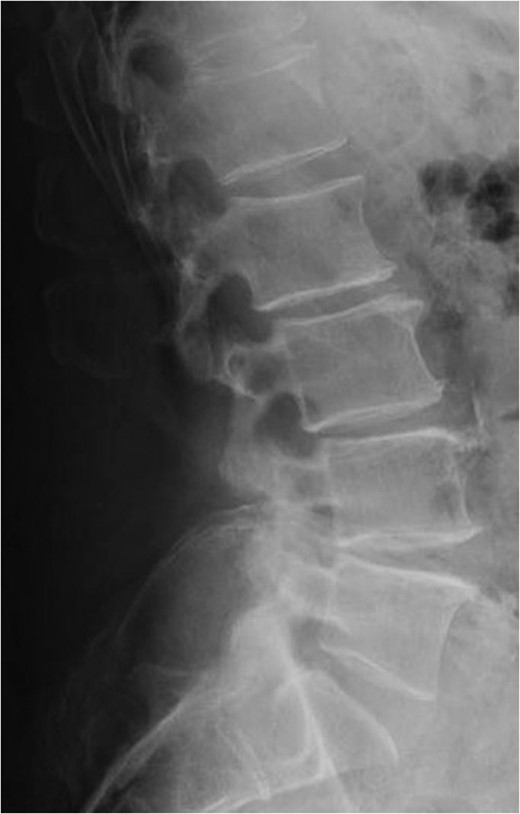

Standing lateral lumbar radiograph obtained 2 weeks following the patient's initial lumbar surgery (L3–S1 laminectomy). No instability is noted on the postoperative image.